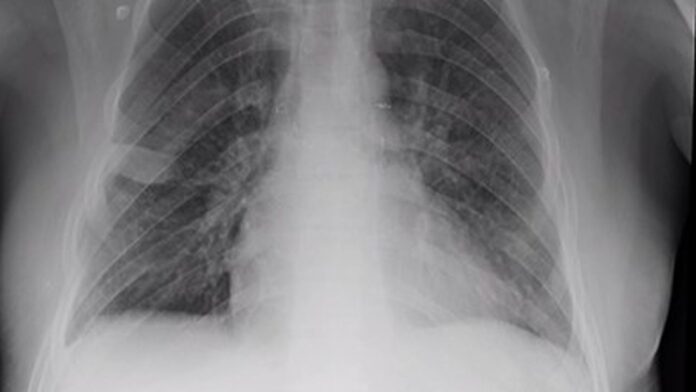

新冠是一种首先侵袭肺部的疾病,严重时会导致呼吸困难病需要人工呼吸装置。如果病人活了下来,他们身体其他组织也会遭受损害,而这种损害的程度仍然属于未知。新冠幸存者往往会有更长期的呼吸问题。

鲁汶大学医院宣布,已为因新冠导致肺部损伤的患者们进行了首批两例移植手术

这两例成功的手术都使有生命危险的患者脱离危险,但医院强调,这类“后冠状病毒感染病例”将会是个例外。